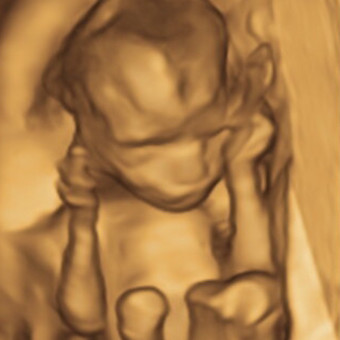

Alyssa and Cadens Baby Registry

Alyssa Monet

Peoria, AZ

November 6, 2024

Thank you for supporting my registry! 🩷